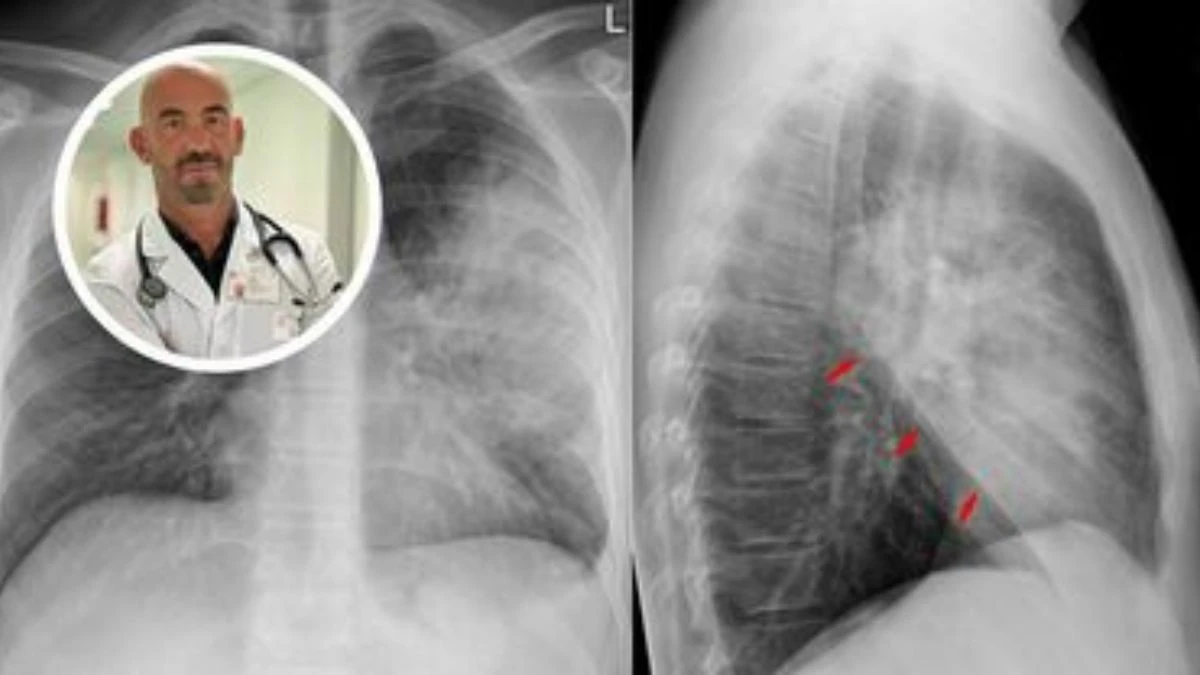

Matteo Bassetti, direttore delle Malattie infettive all’ospedale San Martino di Genova, ha recentemente lanciato un segnale chiaro: «I nostri ospedali sono già oggi pieni di casi di polmonite». Un’affermazione che risuona come un campanello d’allarme in un contesto in cui la pressione sugli ospedali italiani si fa sentire con largo anticipo rispetto alla stagione invernale. Ogni anno, secondo i dati ufficiali, i ricoveri per polmonite superano le 150.000 unità nel nostro Paese, con oltre 9.000 decessi legati direttamente a questa patologia respiratoria. Il trend rischia di aggravarsi con l’arrivo dei mesi più freddi.

La polmonite rappresenta una delle principali cause di ricovero in Italia durante i mesi autunnali e invernali. Si tratta di un’infiammazione degli alveoli polmonari, le strutture responsabili dello scambio di ossigeno nei polmoni. Quando questi si riempiono di liquidi o pus, la funzione respiratoria viene compromessa, con sintomi che possono rapidamente peggiorare fino a richiedere cure intensive.